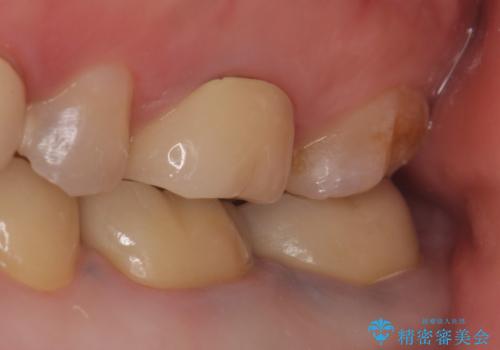

症状の消失を確認後、オールセラミッククラウンによる補綴を行いました。

- オールセラミッククラウン…¥100,000×3、仮歯…¥10,000×3、ファイバーコア…¥20,000×2、精密根管治療費別途費用は治療当時の料金となります

今回用いたオールセラミッククラウンは、ジルコニアフレームという白い素材の上にセラミックを盛っているため審美性が非常に高いのが特徴です。

またジルコニアは人工ダイヤモンドの材料にも使われているほど高い強度を持っており、そのためオールセラミッククラウンは審美性だけでなく、奥歯やブリッジの補綴も可能とするクラウンです。